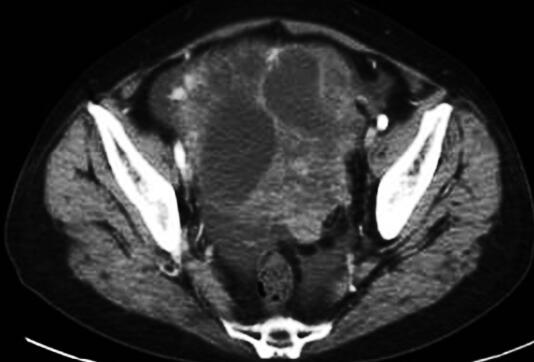

通过再次深入询问病史及进行详细的体格检查得知:患者同时存在胸腔积液和腹水,属于多浆膜腔积液,1个月前因腹胀于妇产医院行妇科检查诊断“子宫脱垂”。虽予治疗,但是未告知患者子宫脱垂原因,查体:下腹部可触及约8cm×10cm大小肿块,边界尚清,质硬,无压痛。入我科后未查妇科,原发灶可能在腹部。进一步行腹部增强CT提示盆腔内可见一巨大肿块影,密度不均匀,CT值为20~33HU,增强后呈不均匀强化,实性部分可见强化,动脉期、静脉期及平衡期CT值分别为70HU、58HU、66HU,最大层面大小约为14.0cm×11.7cm。肝周、脾周及盆腔内可见液性密度影。盆腔肿物考虑为卵巢囊性癌可能性大(图2)。此时,诊断思路豁然开朗,多浆膜腔积液性质为渗出液,原发灶位于卵巢,即卵巢肿瘤伴胸腔和腹腔积液。进一步查糖链抗原125(CA125)为4577U/ml(0~35U/ml),附睾蛋白(HE4)为607pmol/L(0~82.9pmol/L),均明显升高,考虑卵巢恶性肿瘤可能性大。

图2